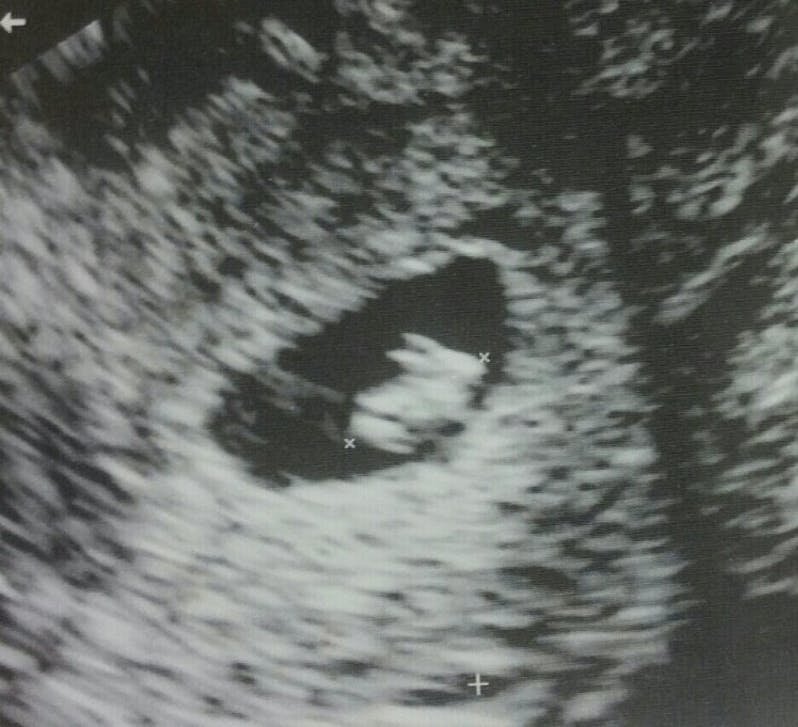

Den gravide kvinde fandt nemlig ud af, at hun ventede noget så særpræget som en kanin – eller det ligner det hvert fald på hendes ultralydsscanning.

Den 33-årige blev – naturligvis – en smule overrasket, da hun opdagede den lille Ninus inde i sin mave. Hun gik dog heldigvis ikke helt i panik. I stedet for kunne hun grine en hel del af det hele – og hun valgte efterfølgende at dele det særprægede scanningsbillede på det sociale medie Reddit, hvor hun blandt andet og meget passende skrev, at hun ”venter en kanin!".